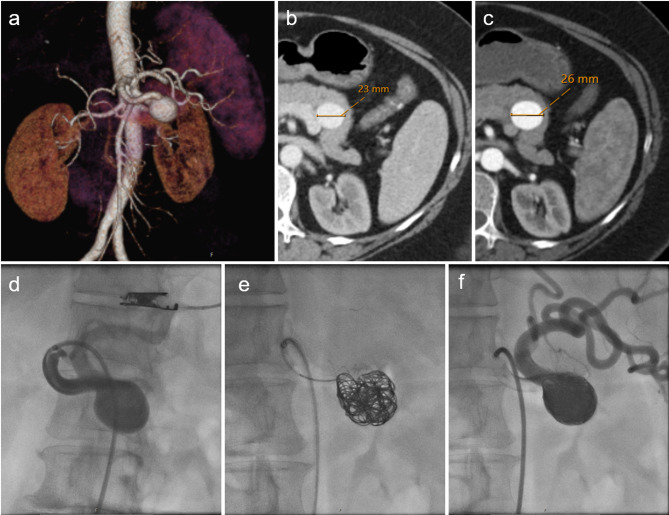

Growth dynamics of splenic artery aneurysms: morphology, comorbidities, and vascular anatomical factors.